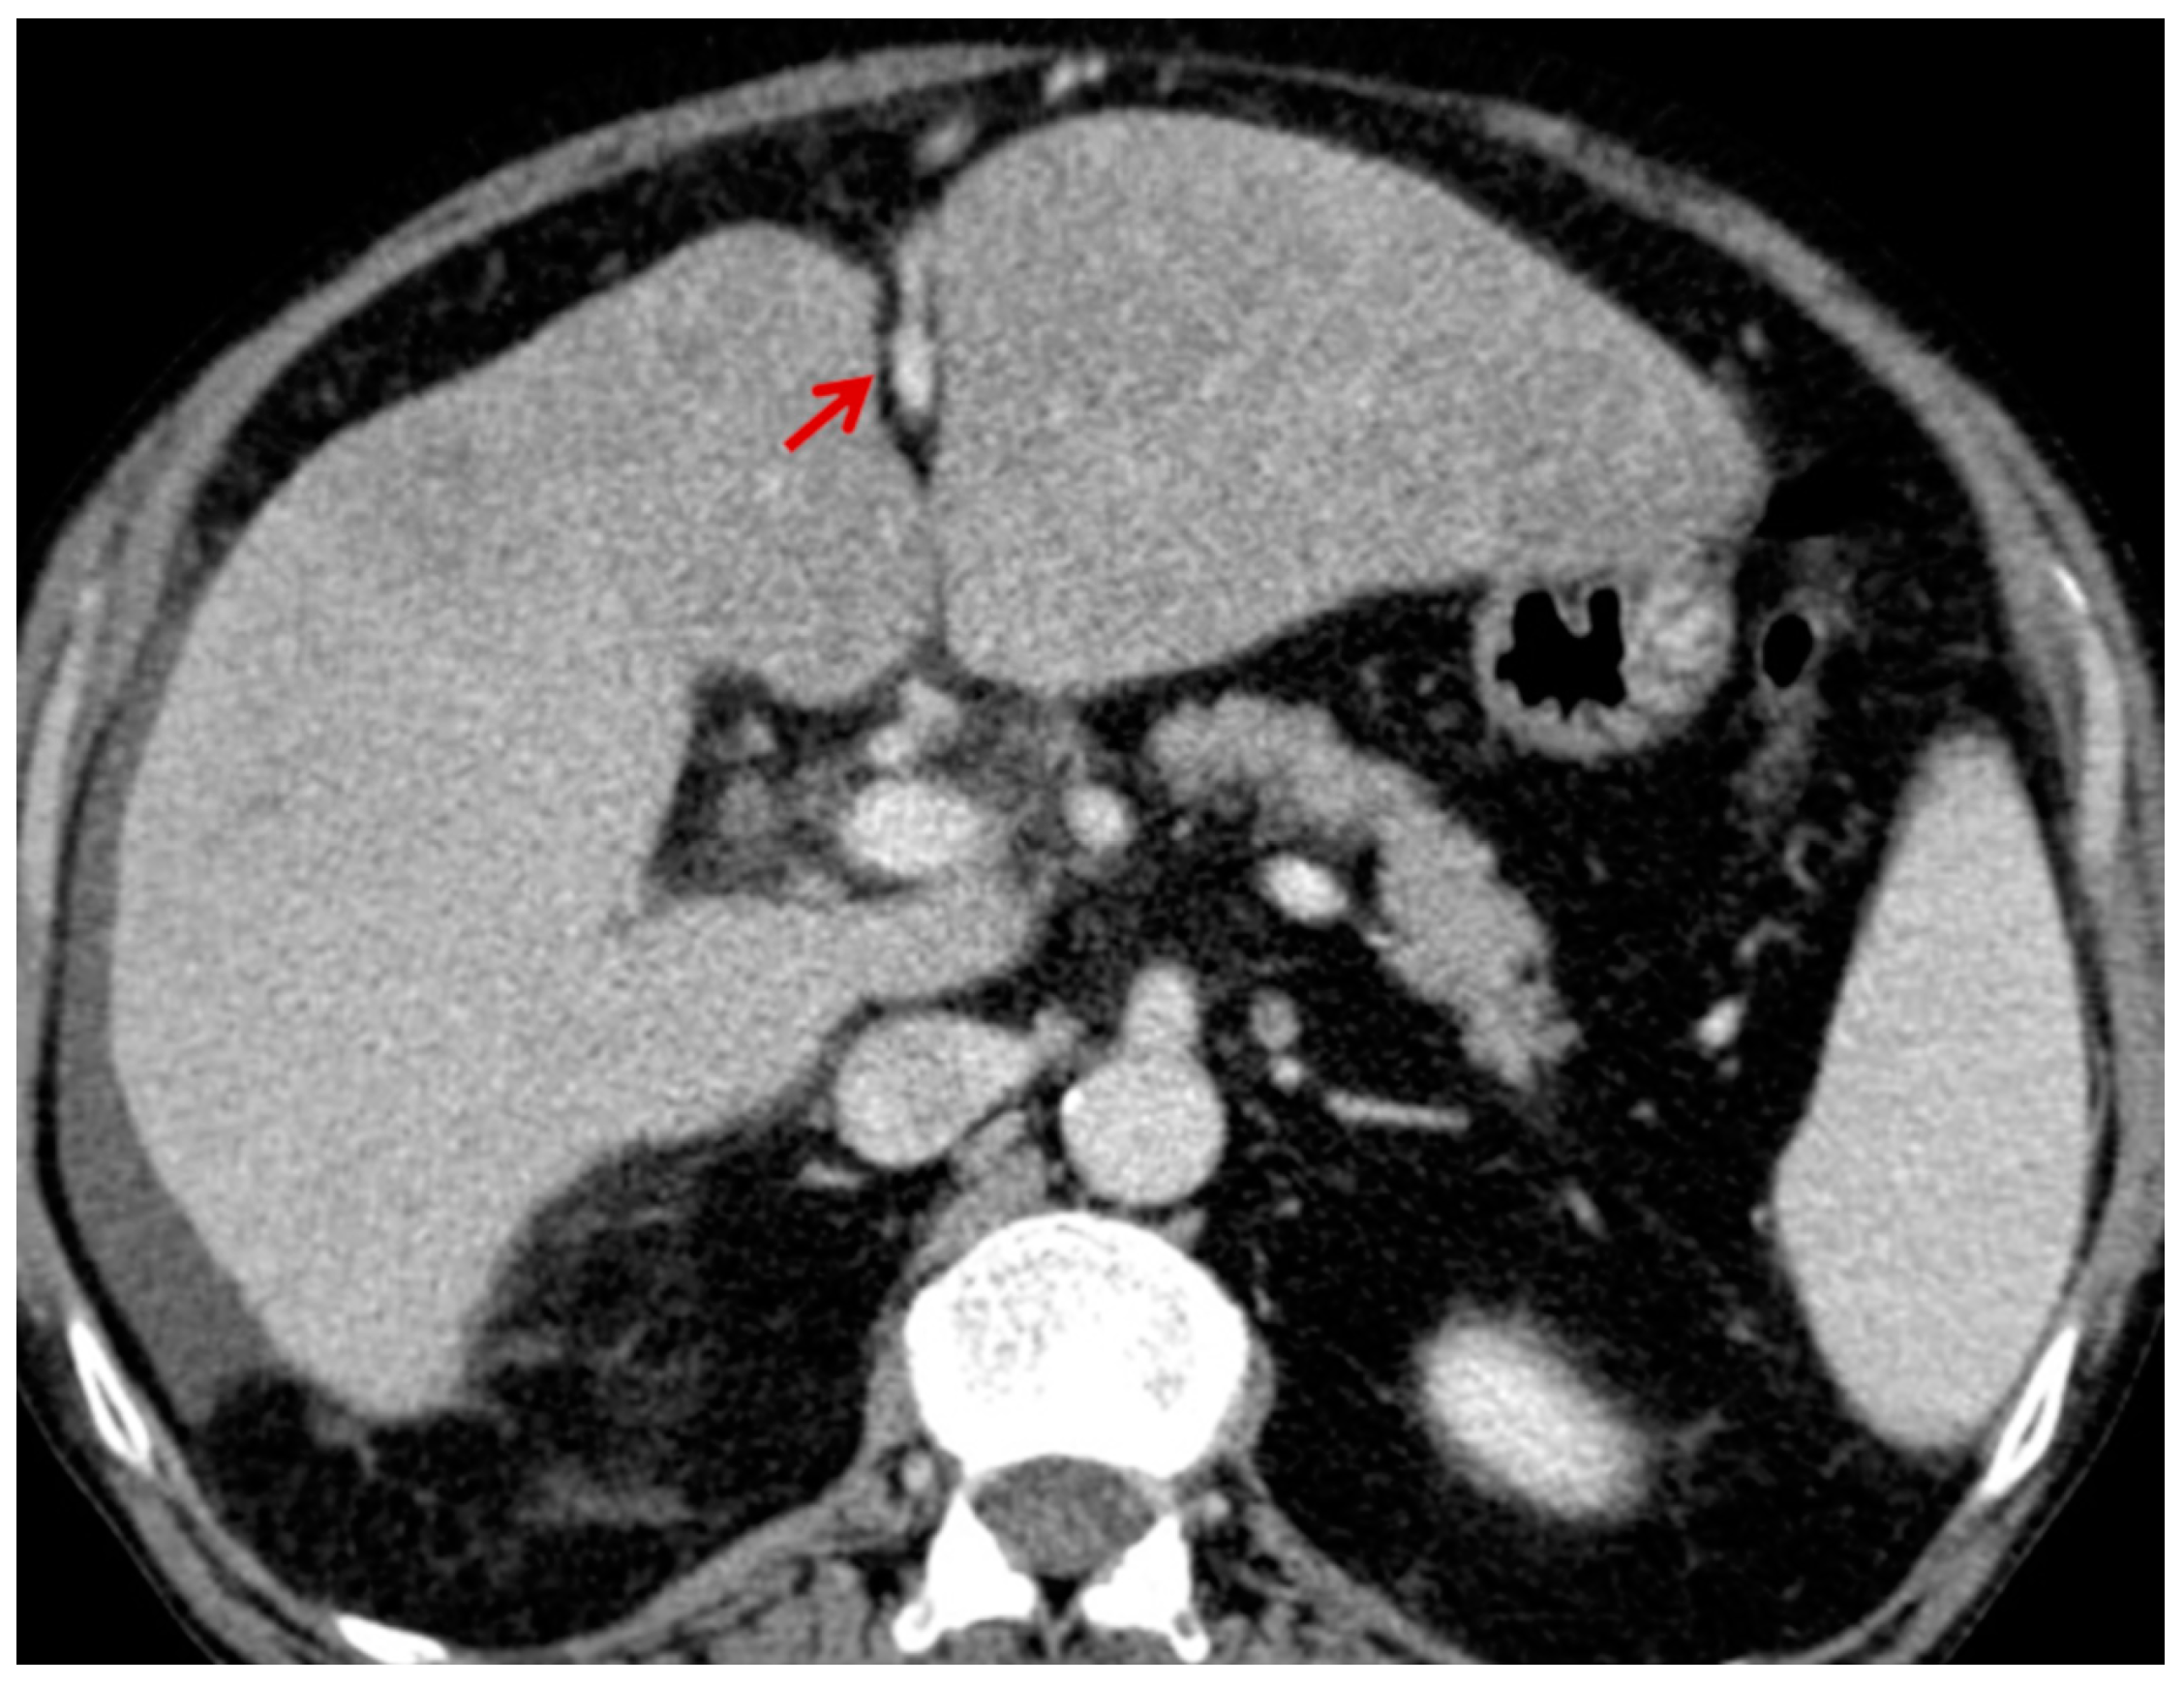

For this study, the images were retrospectively analyzed in consensus by two readers with experience in the field of abdominal imaging. The two readers assessed the following CT features: (1) The presence or absence of paraoesophageal varices and the size(mm) of the largest varix (Figure 1); (2) the presence or absence of paragastric varices and the size (mm) of the largest varix (Figure 2); (3) the largest diameter of the left gastric vein (Figure 3); (4) the presence or absence of splenorenal shunts and the size(mm) of the shunt (Figure 4); (5) the presence or absence of a repermeabilized round ligament and the size(mm) of it (Figure 5).

Figure 3. Axial contrast-enhanced CT shows enlarged left gastric vein (red arrow).